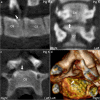

Background: Computed tomography (CT) is used to evaluate body composition and limb osteochondrosis in selection of breeding boars. Pigs also develop heritably predisposed abnormal curvature of the spine including juvenile kyphosis. It has been suggested that osteochondrosis-like changes cause vertebral wedging and kyphosis, both of which are identifiable by CT. The aim of the current study was to examine the spine from occiput to sacrum to map changes and evaluate relationships, especially whether osteochondrosis caused juvenile kyphosis, in which case CT could be used in selection against it. Whole-body CT scans were collected retrospectively from 37 Landrace or Duroc boars with poor back conformation scores. Spine curvature and vertebral shape were evaluated, and all inter-vertebral, articular process and rib joints from the occiput to the sacrum were assessed for osteochondrosis and other lesions.

Results: Twenty-seven of the 37 (73%) pigs had normal spine curvature, whereas 10/37 (27%) pigs had abnormal curvature and all of them had wedge vertebrae. The 37 pigs had 875 focal lesions in articular process and rib joints, 98.5% of which represented stages of osteochondrosis. Five of the 37 pigs had focal lesions in other parts of vertebrae, mainly consisting of vertebral body osteochondrosis. The 10 pigs with abnormal curvature had 21 wedge vertebrae, comprising 10 vertebrae without focal lesions, six ventral wedge vertebrae with ventral osteochondrosis lesions and five dorsal wedge vertebrae with lesions in the neuro-central synchondrosis, articular process or rib joints.

Conclusions: Computed tomography was suited for identification of wedge vertebrae, and kyphosis was due to ventral wedge vertebrae compatible with heritably predisposed vertebral body osteochondrosis. Articular process and rib joint osteochondrosis may represent incidental findings in wedge vertebrae. The role of the neuro-central synchondrosis in the pathogenesis of vertebral wedging warrants further investigation.